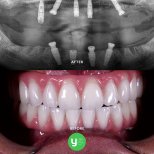

Цей пакет включає встановлення 4 швейцарських імплантатів Straumann Neodent на одну щелепу. Виробник надає довічну гарантію, що забезпечує довгострокову надійність. Доктор Міллер Вієйра Паула, сертифікований ADA імплантолог та автор наукових досліджень, виконує процедуру за методикою негайного навантаження в клініці YeahSmile. Процес складається з двох візитів: встановлення імплантатів та тимчасового протеза протягом 5–6 днів, після чого слідує період загоєння тривалістю 4–6 місяців перед фінальним протезуванням. Вартість становить близько 10 990 $. У ціну «все включено» входять планування на основі 3D КТ, необхідні видалення зубів або синус-ліфтинг, колагенова мембрана та повний супровід консьєрж-сервісу.